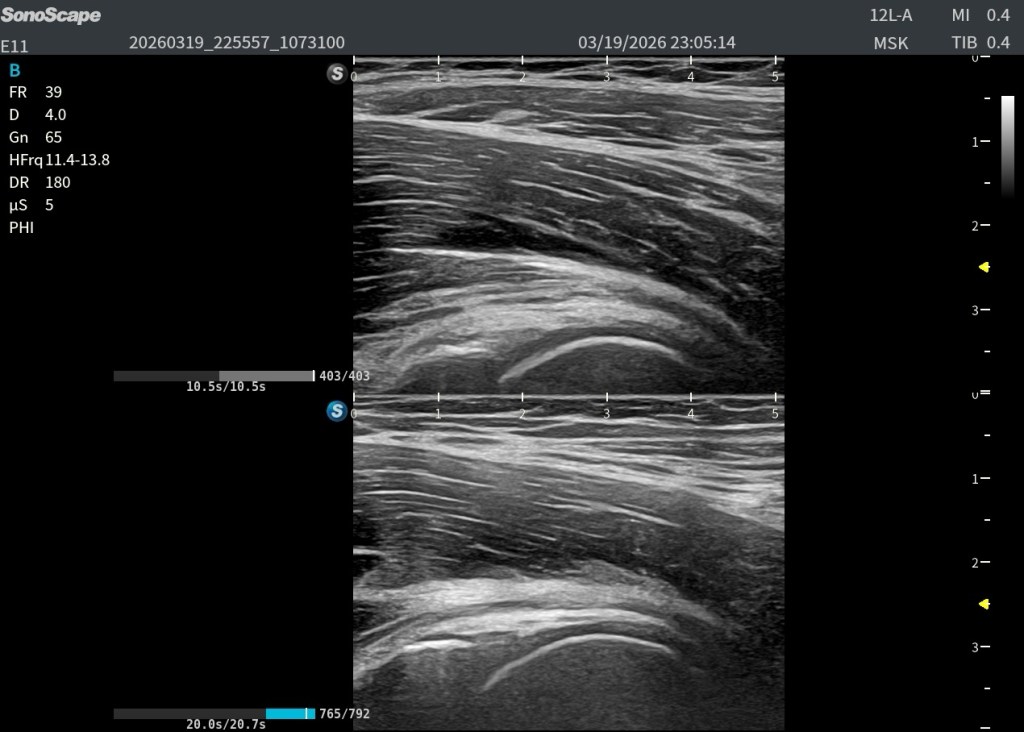

Se realiza ecografía musculoesquelética dirigida al punto de máximo dolor.

A nivel de la cabeza femoral izquierda, en la región profunda del psoas ilíaco, se identifica:

En eje longitudinal (eje largo – línea roja): Imagen anecoica alargada Localizada en las fibras profundas del psoas Con una longitud aproximada de 2,5 cm En eje transversal (eje corto – línea amarilla): La lesión se reproduce claramente, confirmando su existencia siempre en dos ejes. Si no lo veo en 2 cortes, no existe.

👉 La visualización en ambos planos es clave para confirmar que no se trata de un artefacto.

Y comparar…eso siempre nos va a dar un plus.